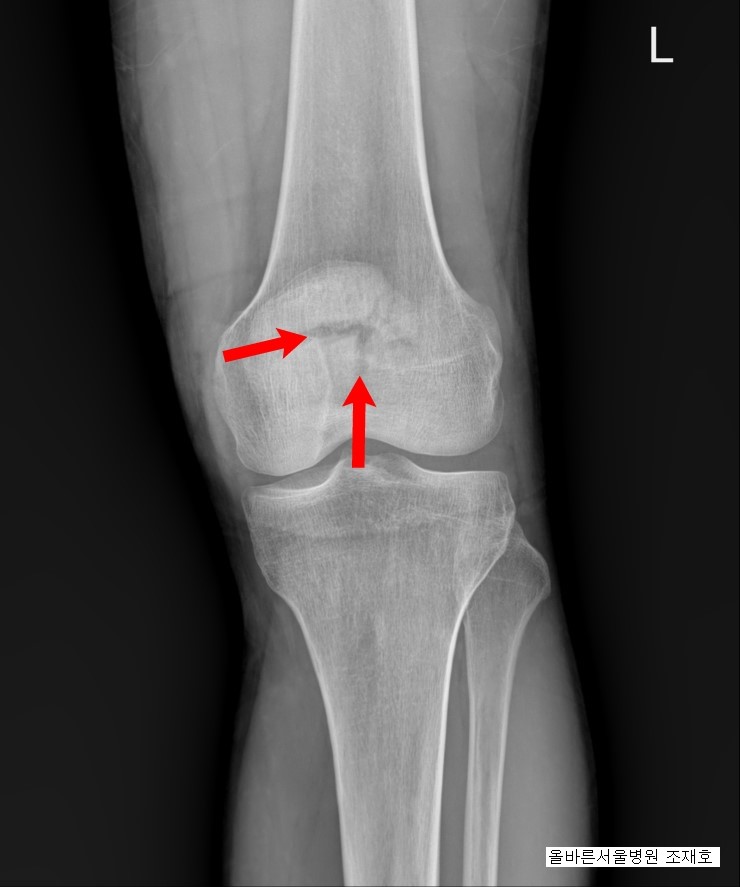

1) 슬개골 골절(슬개골 골절)이란?

슬개골의 구조는 단순하지 않습니다. 대퇴사두근이라는 큰 근육이 붙어 있기 때문에 슬개골에 문제가 생기면 안정적으로 걸을 수 없게 되고 각종 질환에 걸릴 수 있으며 나중에 수술을 하더라도 후유증이 생기기 마련이다. . 그 증상은 다양하지만 대표적인 것이 운동범위의 제한과 통증이며, 골절 시 주사나 석고주사 등은 보행 장애를 유발할 수 있어 고령일수록 이런 현상이 발생하기 쉽다. 골절의 증상이 나타난 후에는 물리치료와 도수치료를 통한 관리가 필요합니다.